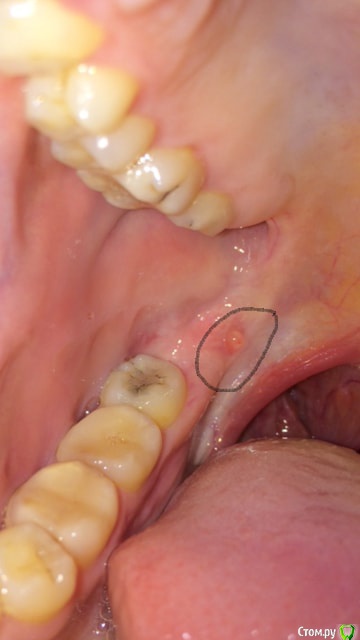

а сегодня вдобавок на крылочелюстной складке вылез водянистый пузырек, см 3 фото.

Прикладываю фото.

post-50717-0-54982000-1525732540_thumb.jpg